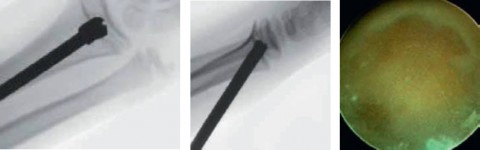

Schrittweise Entfernung der Knochenbrücke

Schrittweise Entfernung der Knochenbrücke mit dem Bohrer und arthroskopische Darstellung der Wachstumsfuge

Um eine zentral in der Fuge gelegene Brücke erfolgreich zu entfernen, muss unter ständiger radiologischer Kontrolle ein Kanal vom angrenzenden (metaphysären) Knochen bis in den Brückenbereich gebohrt werden, wobei die Bohrerdicke den Umfang der Knochenbrücke etwas übersteigt. Anschliessend muss überprüft werden, ob die gesamte Brücke entfernt wurde. Dies führen wir standardmässig mit einem Handgelenksarthroskop durch, mit dem sich im 360 °- Winkel überprüfen lässt, ob in allen Teilbereichen die «gesunde» knorpelige Wachstumsfuge sichtbar ist. Nach Einlage eines Interponats – in der Regel Subkutanfett – zur Rezidivprophylaxe wird die Wunde verschlossen. Teilweise sind weitere Eingriffe im Rahmen derselben Sitzung notwendig, z. B. ein wachstumslenkender Eingriff oder eine Korrekturosteotomie. Anschliessend erfolgen bis zum Abschluss des Skelettwachstums regelmässig Nachkontrollen, um sicherzustellen, dass die Fuge korrekt weiterwächst.